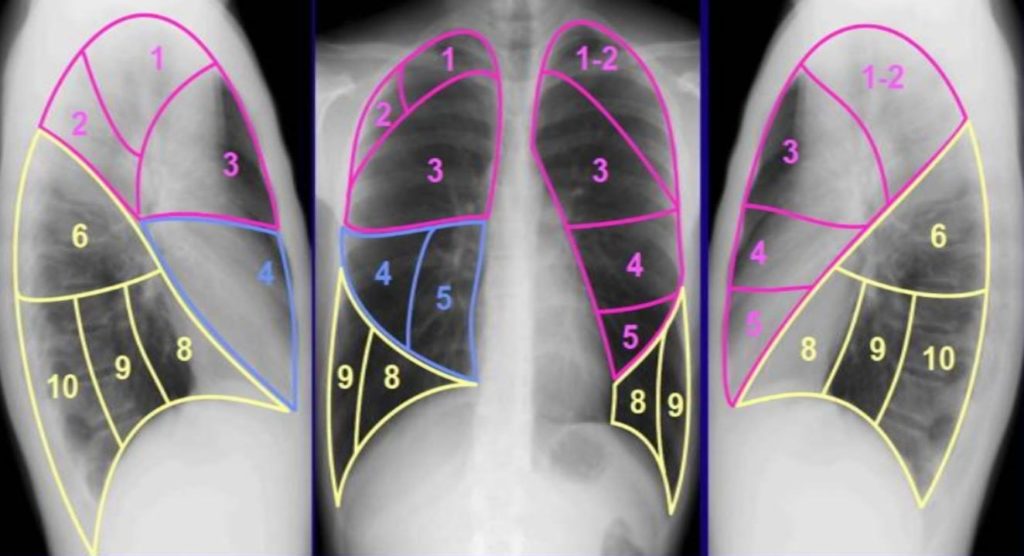

Анатомические изображения сегментов легких различных животных

Раздел: Другие животные